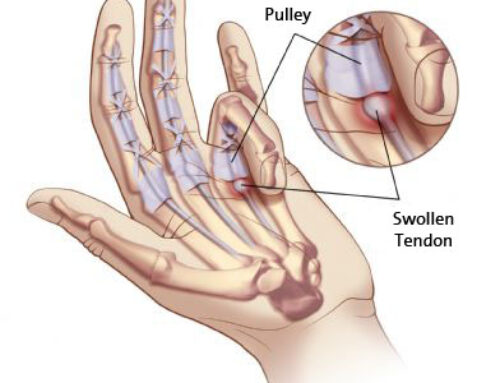

El lavado ecoguiado de calcificación es una técnica mínimamente invasiva destinada a tratar la tendinitis calcificada del hombro u otras localizaciones. Consiste en introducir una fina aguja guiada por ecografía hasta la calcificación y realizar un lavado con suero para fragmentarla y extraerla parcialmente. El objetivo es reducir la presión dentro del tendón y disminuir la inflamación. Es una alternativa eficaz cuando el dolor limita el movimiento o persiste pese a otros tratamientos.

• Dolor en el hombro por tendinitis calcificada sintomática.

• Episodios agudos de dolor intenso por aumento de presión en el tendón.

• Calcificaciones visibles en ecografía que producen dolor mecánico o inflamatorio.